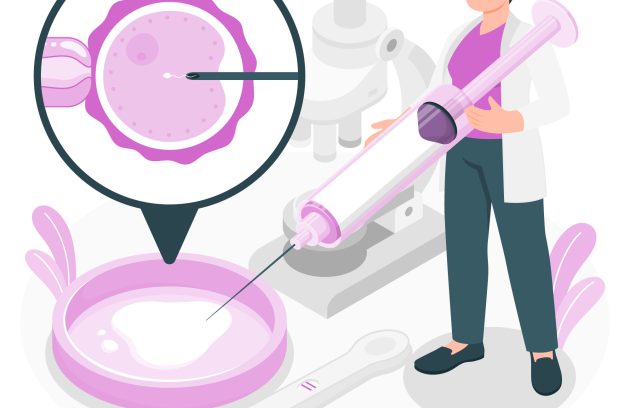

الفرق بين الحقن المجهري وأطفال الأنابيب: أيهما أنسب لحالتك؟

مع تزايد نسب تأخر الحمل، ظهرت تقنيات عديدة لمساعدة الأزواج على تحقيق حلم الأبوة والأمومة. من أشهر هذه…

الحقن المجهري

الحقن المجهري هو علاج من وسائل الإخصاب المساعد يستخدم للمساعدة في الحمل لدى الأشخاص الذين يعانون من مشاكل…

ما هو الحقن المجهري ؟ الخطوات والتكلفة في مصر

الحقن المجهري أصبح من أكثر الحلول الشائعة لعلاج مشاكل تأخر الإنجاب. هذه التقنية الطبية الحديثة تقدم أملًا كبيرًا…